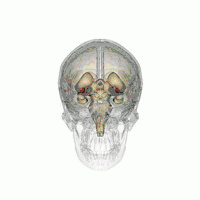

The leads are two coiled wires insulated in polyurethane with four platinum-iridium electrodes that allow delivery of electric charge from the battery pack implanted in the chest wall. The battery is usually situated subcutaneously below the clavicle and rarely in the abdomen. The leads, in turn, are connected to the battery by an insulated extension wire which travels from the chest wall superiorly along the back of the neck below the skin, behind the ear, and finally enters the skull through a surgically made burr hole to terminate in the deep nuclei of the brain.[19] Microelectrodes (usually 1–5) are delivered through the burr holes. A combination of microelectrode recordings, microstimulation, macrostimulation, and neurophysiological mapping at the level of single neurons or local neuronal populations through local field potential analyses are used to increase specificity of placement for the most precise neurophysiologic effect possible.[2]

DBS leads are placed in the brain according to the specific symptoms to be addresses and implantation may take place under local or general anesthesia. A hole about 14 mm in diameter is drilled in the skull and the probe electrode is inserted stereotactically, using either frame-based or frameless stereotaxis.[21] During the awake procedure with local anesthesia, feedback from the individual is used to determine the optimal placement of the permanent electrode. During the asleep procedure, intraoperative MRI is used to image the brain during device placement.[22] The installation of the IPG and extension leads occurs under general anesthesia.[23]